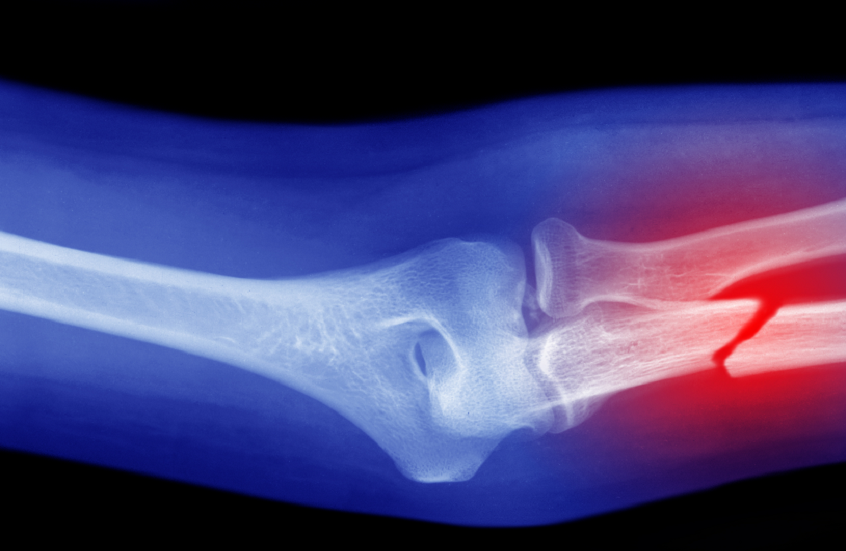

حمية غذائية تقلل من خطر كسور العظام

أظهرت دراسة أجراها علماء من جامعة تشيستر البريطانية أن اتباع حمية البحر الأبيض المتوسط قد يقلل من خطر التعرض لكسور العظام.

قام العلماء أثناء الدراسة بمراجعة بيانات وإحصائيات لـ 30 دراسة سابقة، شملت أكثر من 500 ألف شخص بالغ، وقارنوا بين تأثير حميات غذائية شهيرة على صحة العظام، وهي: حمية البحر الأبيض المتوسط، والحميات منخفضة السعرات، والحميات عالية البروتين، والمنخفضة الكربوهيدرات، وحمية الكيتو.

وأظهرت النتائج أن كثافة العظام لم تتغير بشكل كبير بين معظم متبعي هذه الحميات، ولكن الفوارق كانت مرتبطة بمعدلات الكسور؛ حيث وجد الباحثون أن الأشخاص المتبعين لحمية البحر الأبيض المتوسط كانوا أقل عرضة للإصابة بالكسور، بما في ذلك كسور الورك.

على النقيض من ذلك، ارتبط التقييد الحاد للسعرات الحرارية بارتفاع مؤشرات تدمير بنية العظام، ما يعني أن هذه الحميات قد تضعف العظام على المدى الطويل.

يرى الباحثون أن التأثير الوقائي لحمية البحر الأبيض المتوسط يعود إلى محتواها الغني بالعناصر الغذائية، فهي تعتمد على الخضروات، والفواكه، والأسماك، والحبوب الكاملة، والبقوليات، وزيت الزيتون، وهذه الأطعمة تزود الجسم بالكالسيوم، والمغنيسيوم، وفيتامين K، وهي عناصر مهمة للحفاظ على العظام وتجدد خلاياها، أما بالنسبة للأنظمة الغذائية القاسية التي تهدف لخفض الوزن بسرعة، فقد تؤدي إلى خلل في توازن هذه العناصر المهمة، مما يسرع من عملية هدم الأنسجة العظمية.